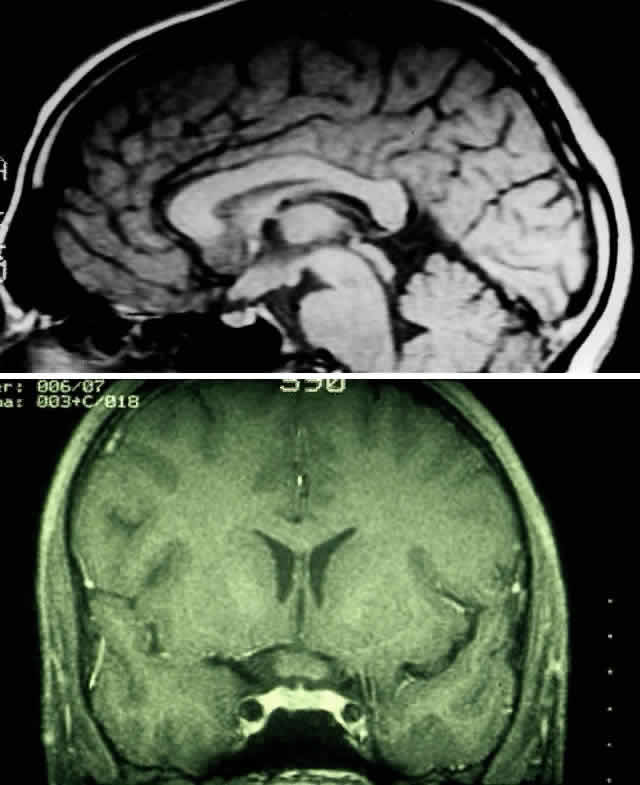

MRI has replaced CT scanning as the optimum test for imaging optic gliomas (Fig. 4 A and B). Optic gliomas have normal to slightly prolonged T1 relaxation times and appear isointense to slightly hypointense to normal brain on T1. Because many of these tumors have prolonged T2 relaxation times, images that are T2 weighted may be used to assess gross tumor margins and posterior extension.72 Optic nerve gliomas often demonstrate minimal enhancement after administration of contrast. To improve MR imaging of optic nerve lesions, a gadopentetate dimeglumine enhancement technique combined with fat suppression can be utilized. Unlike meningiomas, the thickened sheath from arachnoid hyperplasia associated with gliomas will not enhance.77 Although imaging should initially be performed in the axial plane to allow visualization of both the optic nerve and the posterior optic pathways, sagittal views are helpful in demonstrating chiasmal involvement; coronal views can be utilized to delineate intracanalicular tumor.78

Fig. 4. A. T1-weighted sagittal MRI of a patient with neurofibromatosis type 1, demonstrating enlarged optic chiasm consistent with optic glioma. B. T1-weighted coronal image with gadolinium and fat suppression in the same patient, demonstrating the chiasmal glioma.